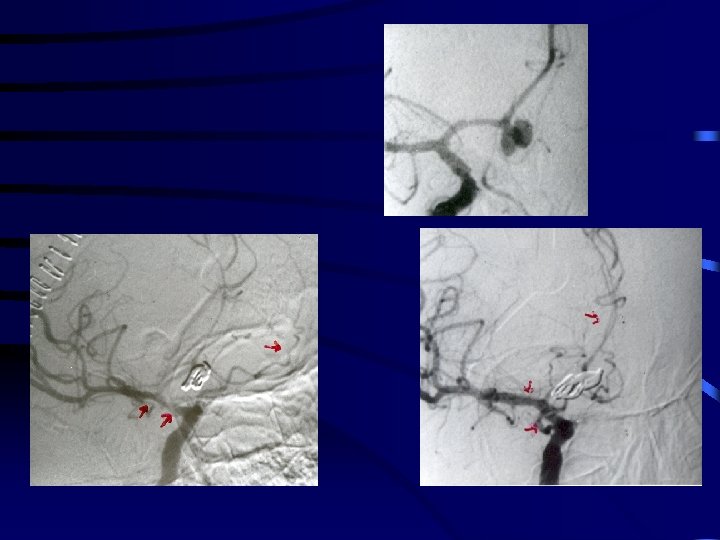

Paediatric SAH Pre -op Post-op

PRE - OP Moya disease POST- OP